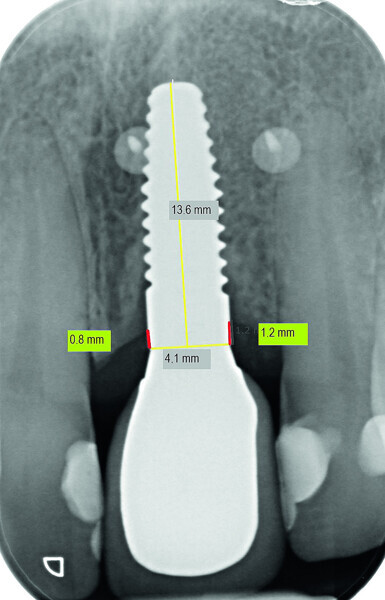

Fig. 13c: Bone resorption was detected after six months and bone gain after 12 months. The yellow line represents the actual implant length (13.6mm). The red lines indicate the mesial and distal distances from the top of the implant to the first bone contact.